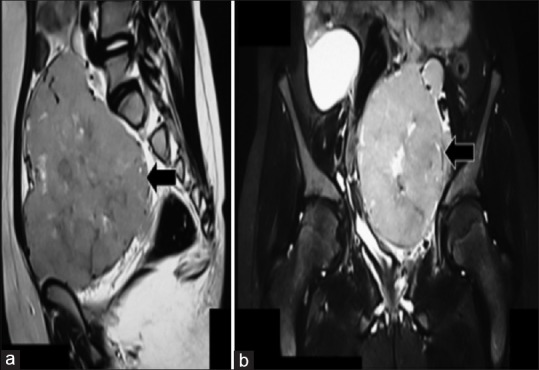

An 11-year-old girl presented with fever for 4 months. On examination, a left-sided suprapubic mass was palpated. Ultrasonography confirmed a mass in the pelvis. A magnetic resonance imaging revealed a large mass located in the pelvis, along with enlarged lymph nodes [Figure 1]. The initial clinical possibility was of a gonadal germ cell tumor. Serum alpha-fetoprotein and beta-human chorionic gonadotrophin were normal. A core biopsy was consistent with a diagnosis of HL, nodular sclerosis (NS) type. Immunohistochemistry was confirmatory; the large atypical cells were positive for CD15/CD30 and negative for CD20. An 18-fluorodeoxyglucose-positron emission tomography-computed tomography (FDG-PET-CT) confirmed FDG avidity of the mass and adjoining nodes. The bone marrow was not infiltrated.

| Figure 1:Magnetic resonance imaging (a - sagittal view, b - coronal view) demonstrated a large pelvic mass (arrows in a and b). The left sided ovary was not distinctly identified. The uterus and urinary bladder were displaced and compressed by the mass